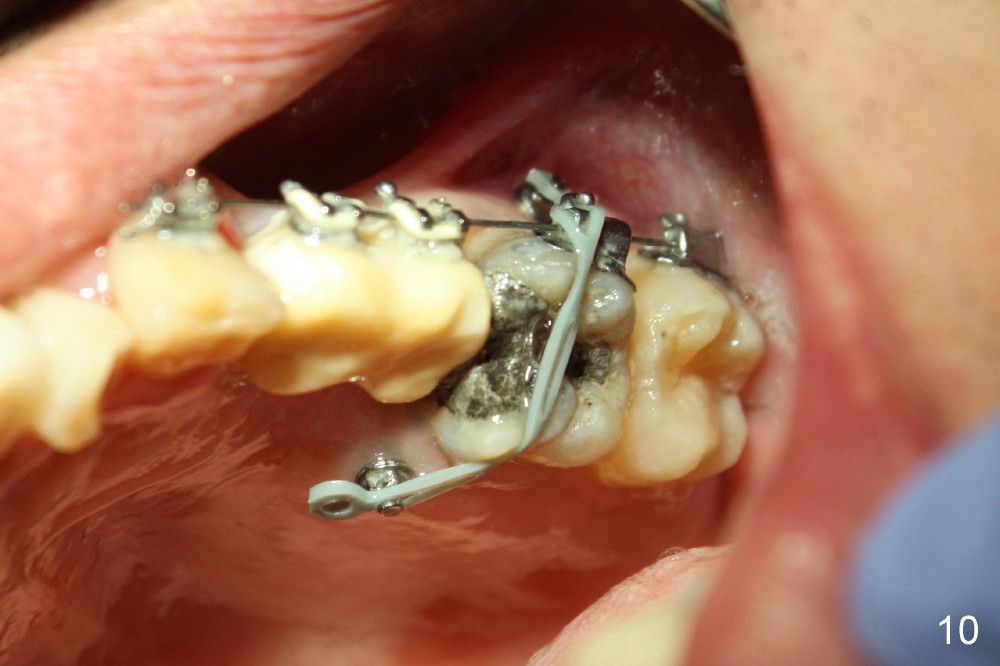

A 51-year-old man needs implants at the sites of #12,13,19 (Fig.1). The teeth #12 and 13 are extracted. An implant is placed at #19 (Fig.2 <). After osteointegration, an abutment is placed (Fig.2 A). The opposing tooth, #14, is found supraerupted. Two mini-implants are placed at the mesiobuccal and distolingual areas of #14 (Fig.3 (mirror view) <) and a power chain (*) is placed for intrusion. In the next 8 months, these 2 mini-implants become loose. Two new mini-implants are placed in the mesiolingual and distobuccal regions (Fig.4 ^). The one in the distobuccal region is loose after a while (Fig.6,7 >). In brief, mini-implants are not efficient in intrusion. At this time, the implants at the sites of #12,13 apparently osteointegrate (3 months post placement) and abutments are placed (Fig.4). Provisional crowns are fabricated (Fig.5). Brackets are placed between #11 and 15 with the bracket at #14 placed more coronally than those of the neighboring teeth (Fig.6-8). Mesially there are two excellent anchorages (#12,13) as well as the mesiolingual mini-implant. The distal anchorage is #15. In the next 5.5 months, the tooth #14 is intruded (Fig.9,10), but the 2nd molar is mobile (not as strong as #14). A longer mini-implant is placed in the distobuccal corner (>, more apical than before (Fig.7)). The distobuccal mini-implant is found to be mobile in 3 weeks (Fig.11). It appears that there is enough clearance for restoration of #19 (Fig.12). Power chains are placed between the mesiolingual mini-implant and #14 buccal tube until the appointment for crown prep. In this way, the lingual cusps may ascend (Fig.13 red arrow), while the buccal ones may descend (black arrow). The occlusal clearance will be more favorable.